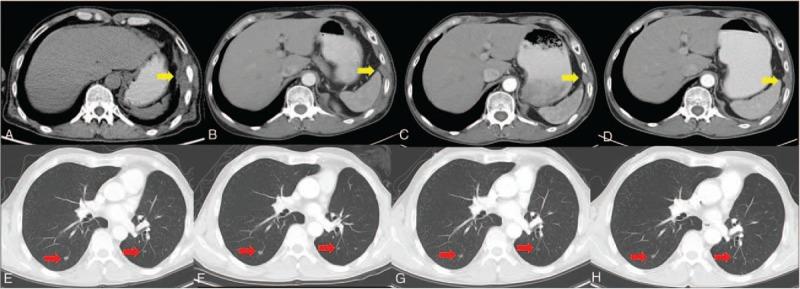

Here, we present a case of a man, heavy smoker who initially presented with stage IA lung adenocarcinoma (LADC). Three years after a lung lobectomy, he was diagnosed with advanced lung squamous cell carcinoma (SCC), according to laboratory, imaging, and pathological examinations.

The case initially had an early-stage LADC with an L858R epidermal growth factor receptor (EGFR) mutation. A subsequent advanced SCC bearing EGFR L858R/T790M mutations occurred 3 years after surgery.

The comprehensive therapy we utilized, including surgical resection for the early-stage lesion and GP chemotherapy and local radiotherapy as the first line therapy along with gefitinib maintenance treatment for the advanced metachronous second primary tumors (MST).

在此,我们报告一例男性病例,该患者为重度吸烟者,最初诊断为IA期肺腺癌(LADC)。肺叶切除术后三年,根据实验室、影像学和病理检查,他被诊断为晚期肺鳞状细胞癌(SCC)。

该病例最初为早期LADC,伴有L858R表皮生长因子受体(EGFR)突变。术后三年发生了随后的晚期SCC,伴有EGFR L858R/T790M突变。

我们采用的综合治疗方法,包括对早期病变进行手术切除,以及将GP化疗和局部放疗作为一线治疗,同时对晚期异时性第二原发性肿瘤(MST)进行吉非替尼维持治疗。